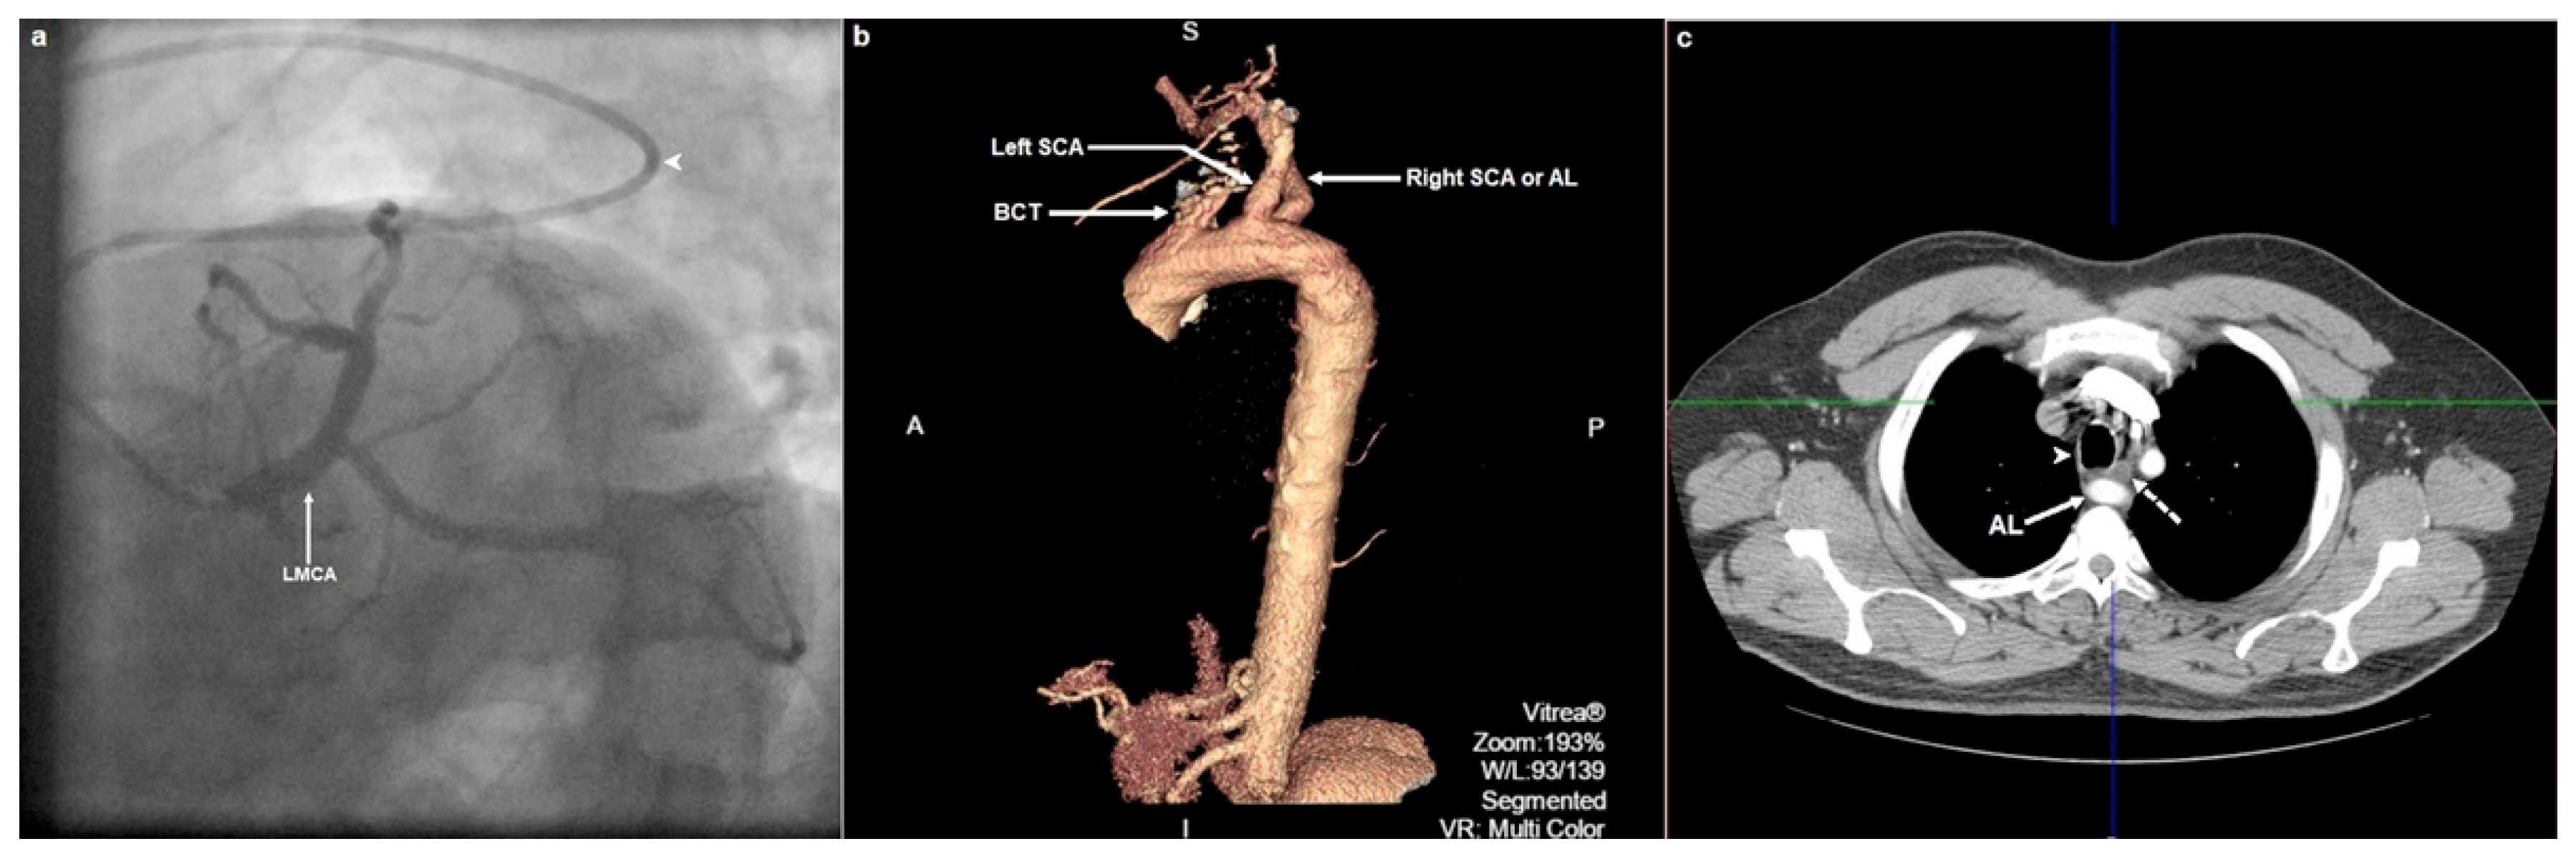

The redundant “Z-like” course of the Judkins left 3.5 catheter made us consider the possibility of an aberrant right SCA or arteria lusoria (AL). Targeted patient interrogation revealed that he had been experiencing dysphagia to solid foods and acid reflux symptoms for about 1 year. Subsequent multislice computed tomography (CT) angiography revealed an AL originating as the last branch of the aortic arch from a position located posterior and to the left of the origin of the left SCA, whereas the right and left carotid arteries were shown to arise from a common trunk (truncus bicaroticus) (Figure 1b; electronic supplementary material, video 1). Aneurysmal dilation of the proximal portion or the aortic origin of AL that would have been compatible with a Kommerell diverticulum was not shown. AL followed a retro-oesophageal course with evidence of oesophageal compression (Figure 1c). Our patient was referred for gastroenterological evaluation. Surgical vascular reconstruction should be considered in case of worsening dysphagia despite conservative measures.

Figure 1. Conventional invasive coronary and computed tomographic angiographic images. (a) Selective left coronary artery angiogram in the left anterior oblique caudal projection. Note, the Judkins left catheter angulation (arrowhead) just before the junction of arteria lusoria (AL) with the aortic arch where it traverses through a wider angle and curves back in order to enter the aortic arch and ascending aorta. Note, also that the course of the catheter from the proximal segment of AL up to the ostium of the left main coronary artery (LMCA) resembles a slanted letter “Z”. (b) Three-dimensional volume-rendered reconstruction of aortic multislice computed tomography (MSCT) angiography depicting a left aortic arch and an aberrant right subclavian artery (SCA) or AL originating distal to the origin the left SCA. A common trunk of right and left common carotid arteries (BCT; bicarotid trunk) is displayed as the first branch of the aortic arch. (c) Axial multiplanar reconstruction of aortic MSCT angiography depicting the oesophagus (dotted arrow) that is compressed between the trachea (arrowhead) and the dorsally located AL (solid arrow).